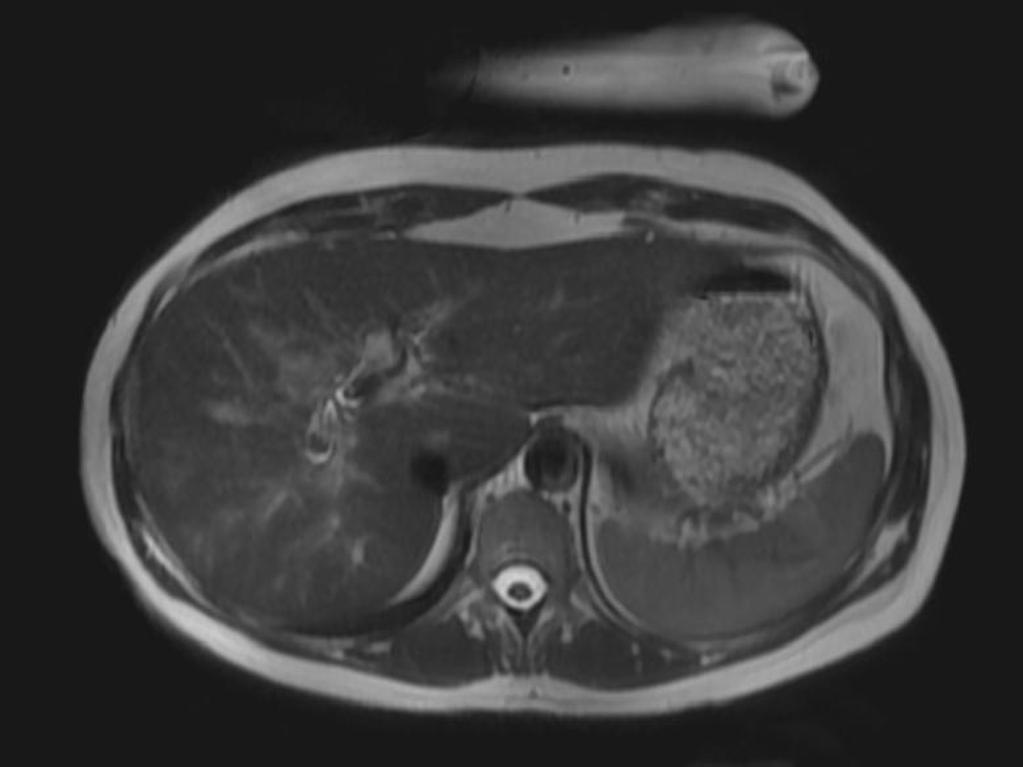

Мрт рака печени

Мрт рака печени 112 фото